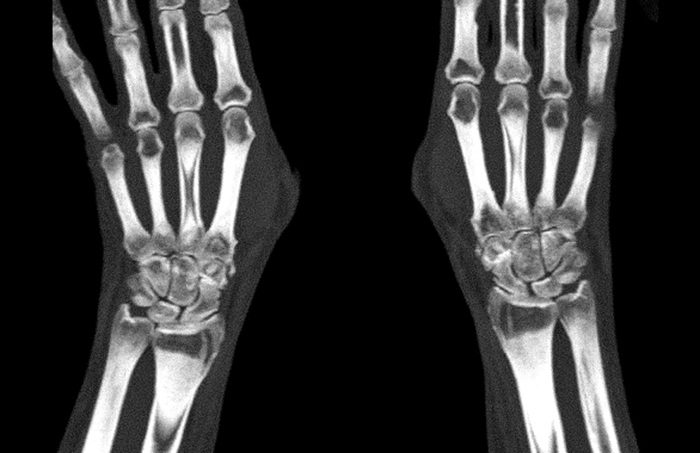

После прохождения процедуры КТ лучезапястного сустава по адресу любой выбранный вами клиники, вы получаете заключение от врача на листе А4 и несколько снимков с трехмерным изображением своего запястья. С этим заключением и снимками весьма желательно посетить своего лечащего врача по месту жительства для получения от него рекомендаций по дальнейшему лечению. Эти рекомендации могут носить медикаментозный или иной характер, но они всегда подобраны индивидуально.